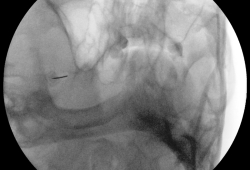

Een fijne naald wordt geplaatst richting het ganglion via het wanggebied, onder röntgendoorlichting. Vervolgens wordt u kort wakker gemaakt om elektrische stimulaties te beoordelen. Op basis van uw feedback over het pijngebied, wordt de juiste zenuwtak geïdentificeerd.